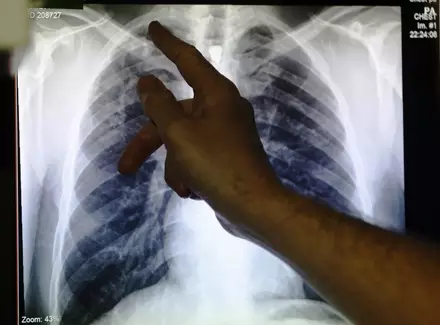

55 больных туберкулезом экс-заключенных разыскивают для лечения в Казахстане

В Казахстане для принудительного лечения разыскивают 55 бывших заключенных, у которых был выявлен туберкулез, передает корреспондент Tengrinews.kz. Об этом на пресс-конференции в Алматы сообщил представитель комитета по защите прав потребителей Министерства национальной экономики Иосиф Куклиновский.

Всего, по данным ведомства, в Казахстане зарегистрировано 589 бывших заключенных, у которых есть туберкулез. Отмечается, что в некоторых случаях освобожденные называют властям ложный адрес. "Сегодня в рамках нового Уголовного кодекса больные туберкулезом после освобождения из мест заключения будут привлекаться к принудительному лечению. Им будет предоставлено лечение в отделении, находящемся на территории той же области, что и колония. Чтобы не было случаев недоезда по указанным ими адресам. В случае соблюдения дисциплины они могут быть направлены на территорию своей области", - сказал он. Он отметил, что к принудительному лечению привлекают по решению суда.

Также в ходе пресс-конференции директор "Национального центра проблем туберкулеза" Тлеухан Абилдаев прокомментировал случай побега бывших заключенных, больных туберкулезом, от врачей в СКО. По его информации, пятеро уже найдены и направлены на принудительное лечение. Один из больных туберкулезом обратился к врачам по собственному решению. "Один самовольно в обычном отделении, остальные - на принудительном лечении. Один больной выехал в другую область, он по регистру прикрепленного населения находится в Алматинской области", - сказал Абилдаев. Он уточнил, что этого больного и еще двоих из СКО сейчас разыскивают, чтобы тоже направить к врачам. Абилдаев напомнил, что освободившиеся из мест лишения свободы люди, у которых есть туберкулез, должны пройти лечение.

Напомним, ранее сообщалось о том, что восемь больных бывших заключенных, у которых был выявлен туберкулез в открытой форме, были объявлены в розыск в Северо-Казахстанской области. Эти лица освободились из мест лишения свободы. В розыск их объявил суд.